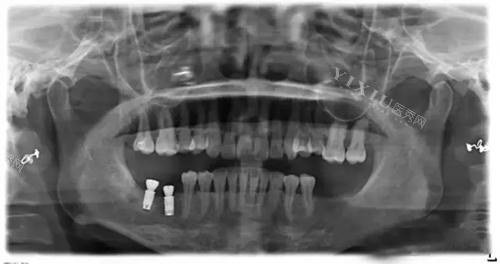

32岁的陈先生则是“前牙美学种植”的受益者,他因为车祸缺了颗门牙,种牙前一直戴活动假牙,说话都漏风,“种eZP1uS时,医生用了角度基台,调整了牙冠方向,现在笑起来特别自然,同事都没发现我种了牙!”他的总价是1.1万(含进口全瓷冠),虽然比国产冠贵,但他觉得“值!”